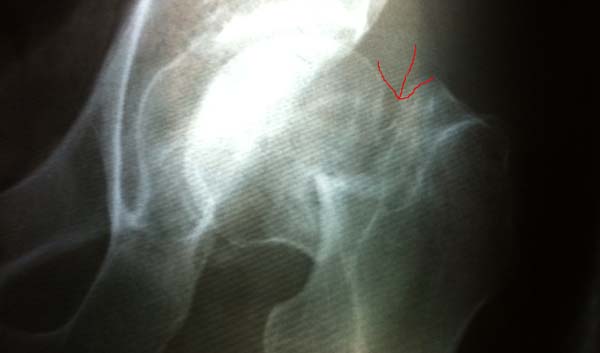

This 48 year old man came into our clinic riding on the back of bike. He was not able to stand. He fell 3 days ago and was not able to get the care. He knew our team was coming so he waited. An x-ray revealed he is a complete fracture of the femoral neck. The only treatment is replacing that hip. We knew it would be expensive but didn't know how much it would cost so we called and the message relayed to us was $200. We thought "Wow, this is great, we can help him". So we sent him to the University for surgery. When he was seen, we were informed it would be $2,000. We had misunderstood the original conversation.

This man with the hip fracture we previously reported.Our financial policy / guidelineprevented us from paying for his surgery but that doesn't prevent our team from showing their love in a meaningful way. He is recovering well and will be able to walk, work to provide for his family in the near future.

Our patient with a fracture hip had successful surgery today and is recovering. Our young child with congenital heart defect is in the hospital and the cost of surgery is fully paid for, wating for surgery. Please continue to pray for her and the family. They already found the real peace!